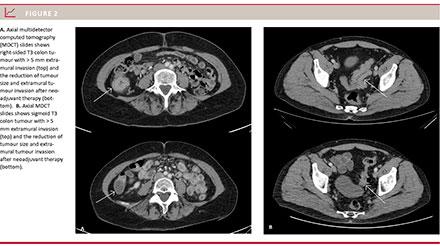

Overall, a reduction in tumour size was observed following NEC (Figure 2). The mean values for all 67 patients are shown in Table 1. The extramural tumour invasion of these advanced colonic cancers decreased from 11 mm to 6 mm after chemotherapy. The number and size of the peritumoral lymph nodes decreased. There was a statistically significant reduction in all variables after NEC compared with baseline (p < 0.001) with no overlap of the 95% confidence intervals (CIs). A tumour size reduction was measured in 90% (95% CI: 80-95%) of the 67 patients, Table 2. As to tumour size according to RECIST 1.1, 55% (95% CI: 43.3-66.5) of the patients (37 of 67) had stable disease. The two patients with tumour growth had an 8% and a 10% increase, respectively. None had progressive disease according to RECIST 1.1. 45% (95% CI: 33.5-56.7) of the patients (30 of 67) responded with a tumour size reduction of > 30%. One patient had complete response with no visible tumour after neoadjuvant chemotherapy (Table 2).

Methods: Computed tomography with IV contrast was acquired from 67 patients before and after up to three cycles of preoperative treatment. All patients had histologically confirmed colon cancer, a T4 or T3 tumour with extramural invasion ≥ 5 mm and no distant metastases or peritoneal nodules. The patients were treated with oxaliplatin and capecitabine. In addition, those with no mutations in the KRAS, BRAF and PIK3CA genes were also treated with panitumumab. Before and after treatment, we measured the tumour diameter in two different planes, the extension of the extramural tumour invasion, and the number and size of enlarged lymph nodes.

Results: The mean tumour length was 7.8 cm (95% confidence interval (CI): 5.3-10.4) at baseline and 4.34 cm (95% CI: 4.0-4.9) after treatment. The mean extramural tumour invasion was 10.6 mm (95% CI: 9.5-11.8) at baseline and 5.7 mm (95% CI: 4.7-6.7) after treatment. The mean number of enlarged lymph nodes was 4.1 (95% CI: 3.4-4.9) at baseline and 2.1 (95% CI: 1.4-2.7) after treatment. According to RECIST 1.1, 45% (95% CI: 34-57) of the patients had a response and 55% (95% CI: 43-67) had stable disease. None of the patients showed progressive disease.